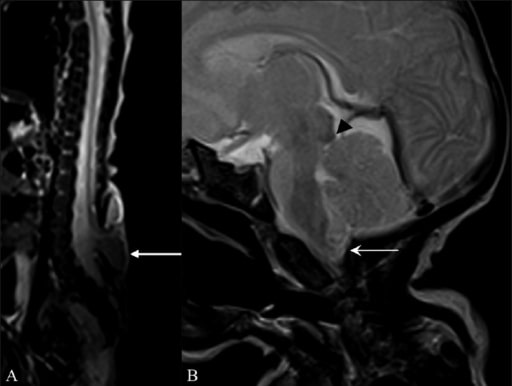

Magnetic resonance imaging (MRI) findings suggestive of Arnold–Chiari II malformation

Sagittal T2W whole-spine MRI (A) shows a meningomyelocele (arrow) opposite the L5 and S1 vertebrae. Sagittal T2W MRI of the brain (B) shows a small posterior cranial fossa, with herniation of the cerebellar vermis and tonsils (arrow) through the foramen magnum with tectal beaking (arrowhead).